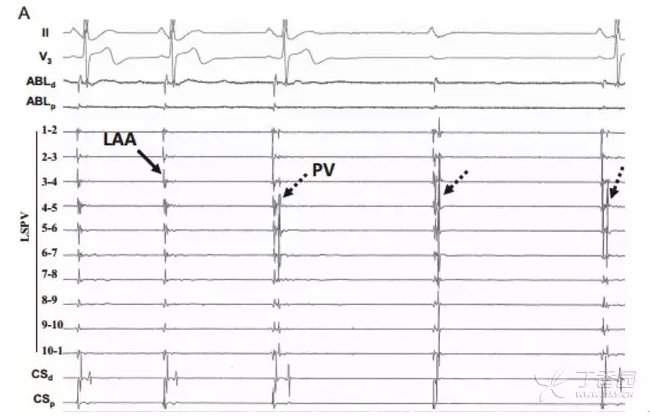

肺静脉隔离后需要分别检测各个肺静脉电传导的恢复情况,每次检测腺苷用量在 6~24 mg,出现 2 度 II 型或 3 度房室传导延迟组织时不再增加腺苷剂量,根据腔内图判断电传导恢复的部位,再次进行消融,消融后再次应用腺苷检测是否存在肺静脉电传导的恢复,直至达到「真正的肺静脉隔离」(图 2)。

图 2 腺苷实验中显示肺静脉传导恢复,并指导进一步的射频消融。 LAA:左房电位;PV:肺静脉电位